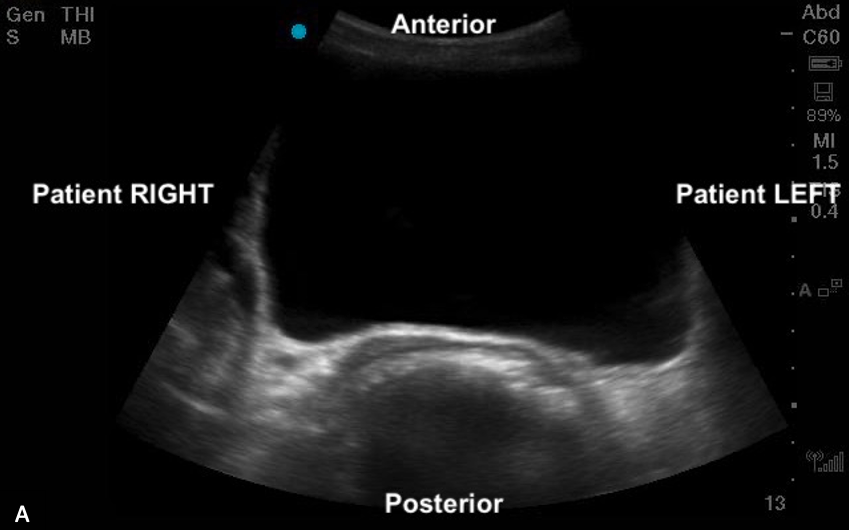

When scanning the bladder, like with any ultrasound, the transverse plane provides a cross-sectional view, with patient right on the screen’s left, patient left on the screen’s right, and anterior in the near field and posterior in the far field. In the sagittal plane, cranial is on the screen’s left, caudal is on the screen’s right, with anterior in the near field and posterior in the far field.

Figure 5ab: Transverse and sagittal bladder views with orientation labels

Figure 9ab: Transverse bladder scan sonoanatomy in female (a) and male (b) chidlren.